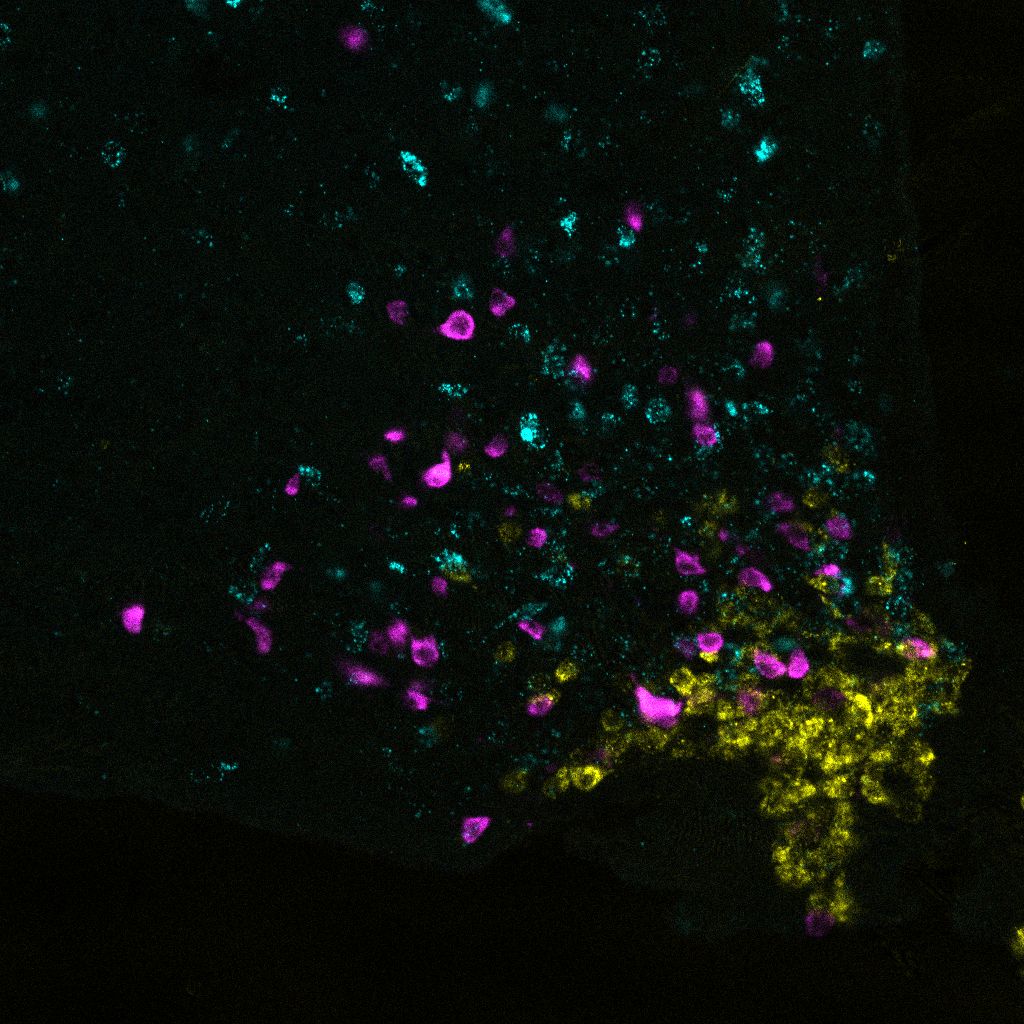

For example, he was the first to show the central role of only about 3,000 so-called AgRP cells in the hypothalamus, a region of the brain important for many of the body’s hormonal processes. Using pioneering techniques, he showed that this group of nerve cells is responsible for how much we eat and how much glucose the liver releases by converting fat back into sugar. These cells also regulate how sensitively our body’s cells react to insulin. In addition, he discovered that they cease to react to insulin in the case of obesity. They are said to become insulin-resistant, and can no longer function properly. His extensive research of the AgRP cells provided the basis for new approaches to develop drugs to treat obesity caused by insulin resistance.